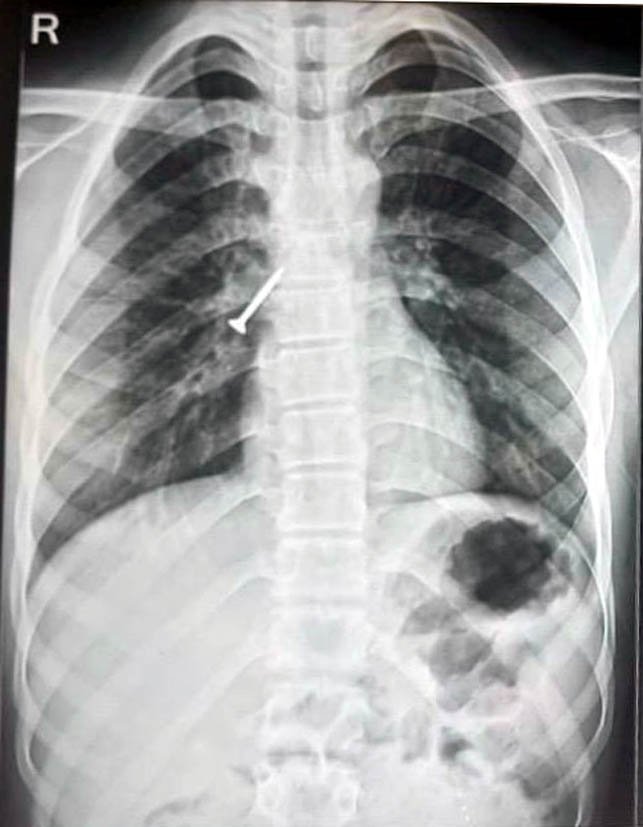

उदयपुर । रवींद्रनाथ टैगोर मेडिकल कॉलेज के अधीन संचालित संभाग के सबसे बड़े टी.बी. एवं चेस्ट अस्पताल, बड़ी के चिकित्सकों ने एक जटिल मामले में 17 वर्षीय युवक की श्वास नली में फंसे 32×4 मिमी के लोहे के स्क्रू को बिना किसी चीर-फाड़ और बिना मरीज को बेहोश किए बाहर निकालने में सफलता हासिल की है। मरीज को 25 अप्रैल को अस्पताल में भर्ती किया गया और स्थिति की गंभीरता को देखते हुए अगले ही दिन 26 अप्रैल को सफलतापूर्वक प्रोसीजर संपन्न किया गया।

सहायक प्रोफेसर डॉ. महेश माहिच ने बताया कि युवक सुथारी का काम करते समय गलती से एक लंबा स्क्रू निगल गया था, जो सीधे उसके दाएं फेफड़े की श्वास नली में जा फंसा। इसके कारण मरीज को लगातार खांसी, छाती में दर्द और बलगम में खून आने की गंभीर समस्या हो गई थी।